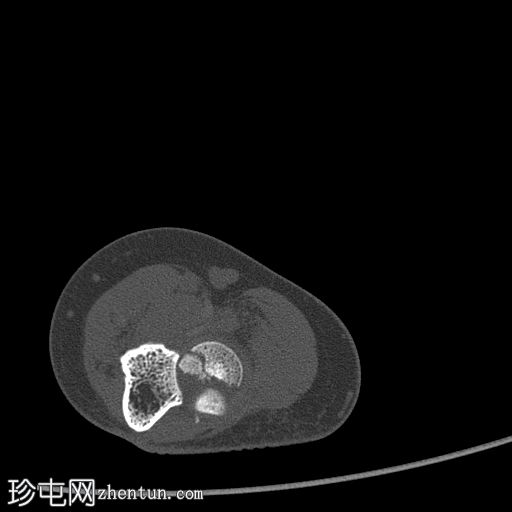

轴向软组织窗

显示整个桡骨头粉碎性骨折,特征为两个以上大骨折块,以及倾斜且受压的关节节。

这表明该骨折为不稳定骨折,根据Mason桡骨头骨折分型,为IIIC型。

远端肱骨和可见尺骨未见骨折征象。

此外,由于关节积血导致关节扩张,肘关节脂肪平面弯曲。